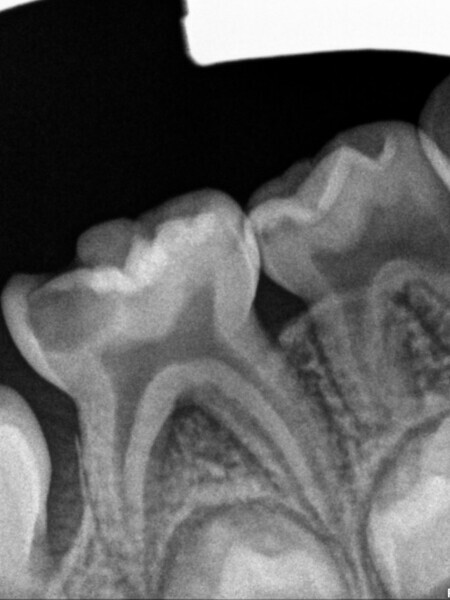

Cas 1 (Figs 1-4)

Cette patiente âgée de 4 ans et 7 mois présentait une douleur qui affectait la seconde molaire temporaire inférieure droite depuis plusieurs jours. L’examen clinique a révélé un gonflement du versant vestibulaire de la gencive et un œdème facial, ainsi qu’une carie occlusale profonde.Un diagnostic de nécrose pulpaire et d’abcès apical symptomatique ayant été posé, un traitement a été prescrit à la patiente, afin de maîtriser l’infection aiguë, et un nouveau rendez-vous a été fixé après l’antibiothérapie. Lors du deuxième rendez-vous, elle ne présentait plus aucune douleur et l’abcès buccal s’était partiellement résorbé. Il a été décidé de procéder à une pulpectomie et à la restauration de la dent. Dans ce cas, la dent présentait une extrusion excessive de matériau d’obturation. Après 15 mois, la réévaluation a confirmé l’absence de signes cliniques ou radiologiques pathologiques, et une apposition osseuse était visible dans la zone de la furcation.